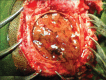

Extradural hematoma (EDH) in absence of trauma is a rare entity with only few cases reported in literature. The various causes reported include: Vascular malformation of dura, coagulopathies, sinus infection, middle ear or orbital infection, and tumor. Occurrence of spontaneous EDH as a complication of sickle cell disease is even much rarer. We report a case with sickle cell disease who presented with spontaneous extradural and subgaleal hematomas following an episode of vaso-oclusive crisis. He was managed successfully with surgery. The association of epidural hematomas in sickling hemoglobinopathies is reviewed. In all cases, we noticed one episode of sickle cell crisis just before the occurrence of spontaneous EDH. Perhaps this crisis puts an extra demand over the hematopoietic skull tissue disrupting inner and outer skull margins leading to spontaneous EDH and subgaleal hematoma.